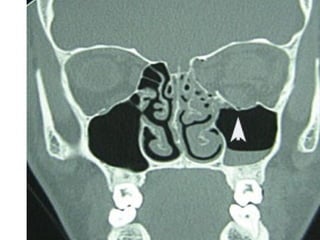

Radiographic Evaluation

• CT scan of the orbits

• Plain films not useful due to a high rate of

false negatives and non-diagnostic studies